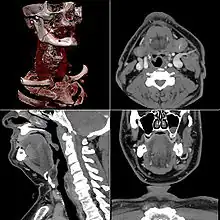

Computed tomography

Computed tomography or CT scan (previously known as CAT scan, the "A" standing for "axial") uses ionizing radiation (x-ray radiation) in conjunction with a computer to create images of both soft and hard tissues. These images look as though the patient was sliced like bread (thus, "tomography" – "tomo" means "slice"). Though CT uses a higher amount of ionizing x-radiation than diagnostic x-rays (both utilising X-ray radiation), with advances in technology, levels of CT radiation dose and scan times have reduced.[9] CT exams are generally short, most lasting only as long as a breath-hold, Contrast agents are also often used, depending on the tissues needing to be seen. Radiographers perform these examinations, sometimes in conjunction with a radiologist (for instance, when a radiologist performs a CT-guided biopsy).